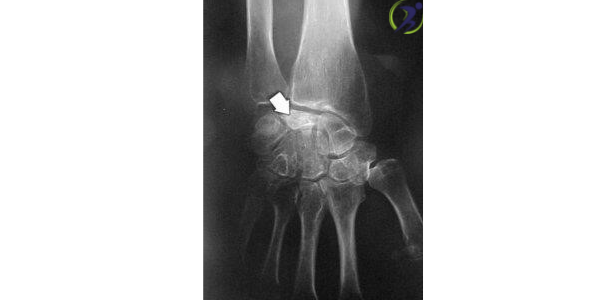

Giai đoạn 3

Trong giai đoạn 3, xương chết bắt đầu sụp lún và vỡ thành nhiều mảnh. Khi xương bắt đầu bị gãy, các xương xung quanh có thể bắt đầu thay đổi vị trí.

Trong giai đoạn này, bệnh nhân thường cảm thấy đau ngày càng tăng, yếu khi cầm nắm và cử động cổ tay bị hạn chế.